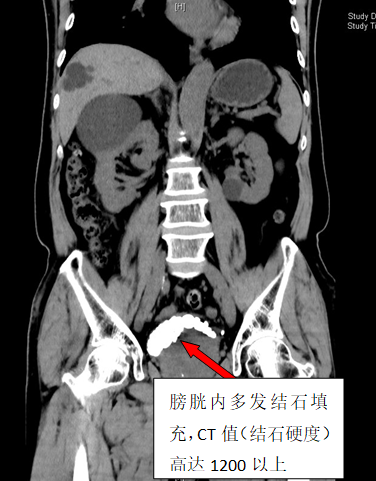

79岁李雄(化名)四年来一直被反复的尿频、血尿、下腹胀痛不适所困扰。在家人多次劝说下,他来到91短视频 泌尿外科二区就诊。CT检查结果显示李大爷膀胱内布满了30余枚结石,犹如月球表面的环形山,其中最大的那颗直径达3厘米,几乎占据了膀胱1/3的空间。

手术当天,泌尿外科二区团队凭借精湛的技术和丰富的经验,为李大爷实施了经尿道钬激光碎石手术。整个碎石过程历时2小时,医护人员精准操作,共发出13800次激光脉冲,将30枚结石打碎取出。术后CT三维重建显示,李大爷的膀胱腔隙内结石已清除干净。